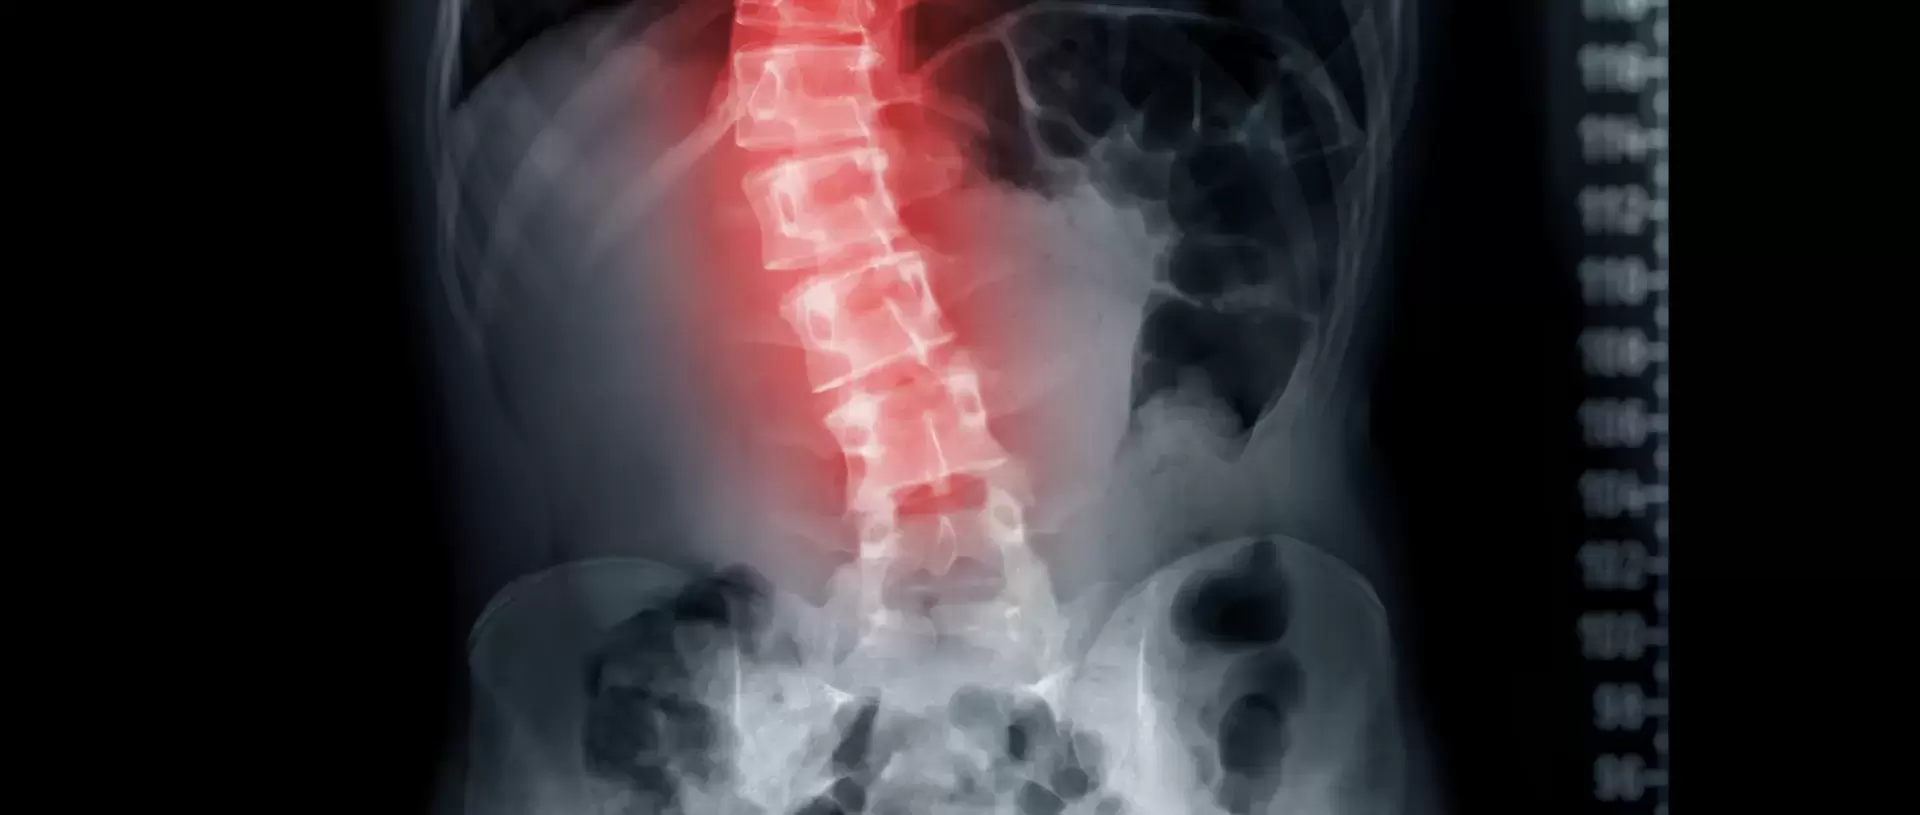

What is Scoliosis and how can Rolfing® help?

Scoliosis, with its characteristic lateral curvature of the spine, is about the whole body. Its causes are complex and include genetic predisposition, imbalances in spinal growth between the anterior and posterior regions, and irregularities in the connective tissues, skeletal muscles and nerves.